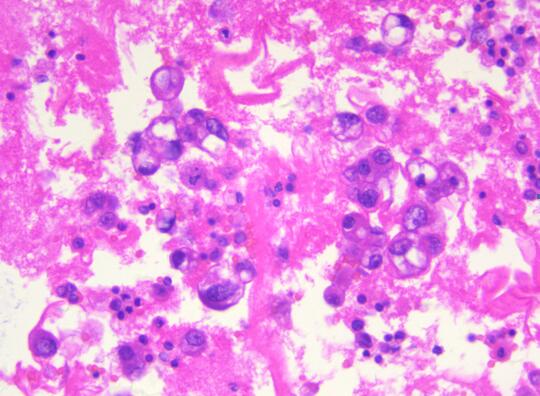

患者,女性,55岁,因腹胀不适半月余,加重乏力5天,盆腔B超提示附件包块。为了明确诊断,临床穿刺抽取500ml血性腹水做病理检查。病理科在接收到患者的腹水标本后,首先做了涂片的细胞学检查,初步提示恶性瘤细胞。在与临床大夫沟通后,科室将剩余的腹水制成了细胞蜡块,行石蜡包埋(图一)并加做了免疫细胞化学染色。免疫细胞化学结果显示Pax-8、ER、WT-1阳性(图二),同时标记间皮的指标阴性。因此,通过细胞蜡块技术该患者可明确诊断为“腺癌,卵巢来源可能性大”。随后患者进行了8次化疗,病情有所缓解,无腹胀,肿瘤系列恢复正常。

细胞蜡块的制备过程经历了沉淀和多次离心,最大限度地保留了癌细胞,减少了细胞丢失,降低了漏诊率。同时,恶性肿瘤的细胞蜡块均可进一步通过免疫细胞化学法确定癌细胞是肺来源、胃肠道来源、乳腺来源、卵巢来源、间皮来源还是淋巴细胞来源。再次,细胞蜡块切片更接近组织学,图像背景清晰,易于镜下观察,大大提高了阳性检出率。最后,细胞蜡块制作程序简单,成本不高,最重要的是细胞蜡块可连续切片进行分子检测,为精准诊断和临床个体化用药提供参考依据。该技术的成功应用大大提高了浆膜腔积液细胞诊断的阳性率,弥补了传统细胞学检查存在的一些缺陷,提高细胞病理诊断在临床的认可度。推动该技术的广泛应用,将对乐鱼手机站入口精准细胞学诊断提供强有力的保障。